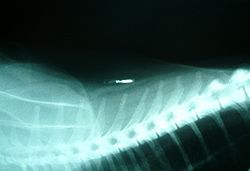

رقاقة مزروعة في قطة.

إن زرع رقاقة هو التعرف على الدوائر المتكاملة التى توضع تحت الجلد لكلب ، أو قط ، أو حصان ، أو الحيوانات الأخرى. والرقائق حوالى حجم حبة كبيرة من الأرز ، وتستند إلى إيجابيات RFID (التكنولوجيالتحديد الهوية بترددات الراديو) .

في الكلب و القط ، فإن الرقائق عادة ما تدرج تحت الجلد في الجزء الخلفي من الرقبة ، وبين لوحي الكتف على خط الوسط الظهري. الحيوانات الأليفة في قارة أوروبا ا قد تكون استثناء لأنهم يحصلون على الزرع في الجانب الأيسر من الرقبة, وطبقا لأحد المراجع.[18] ويمكن غالبا أن يتم الكشف على الشريحة يدويا بالكشف من قبل المالك عن طريق تحسس الجلد بلطف في هذا الموضع. فإنه يبقى في مكان وطبقات رقيقة من النسيج الضام المتوافق حيويا حول الزجاج الذي يغلف به.